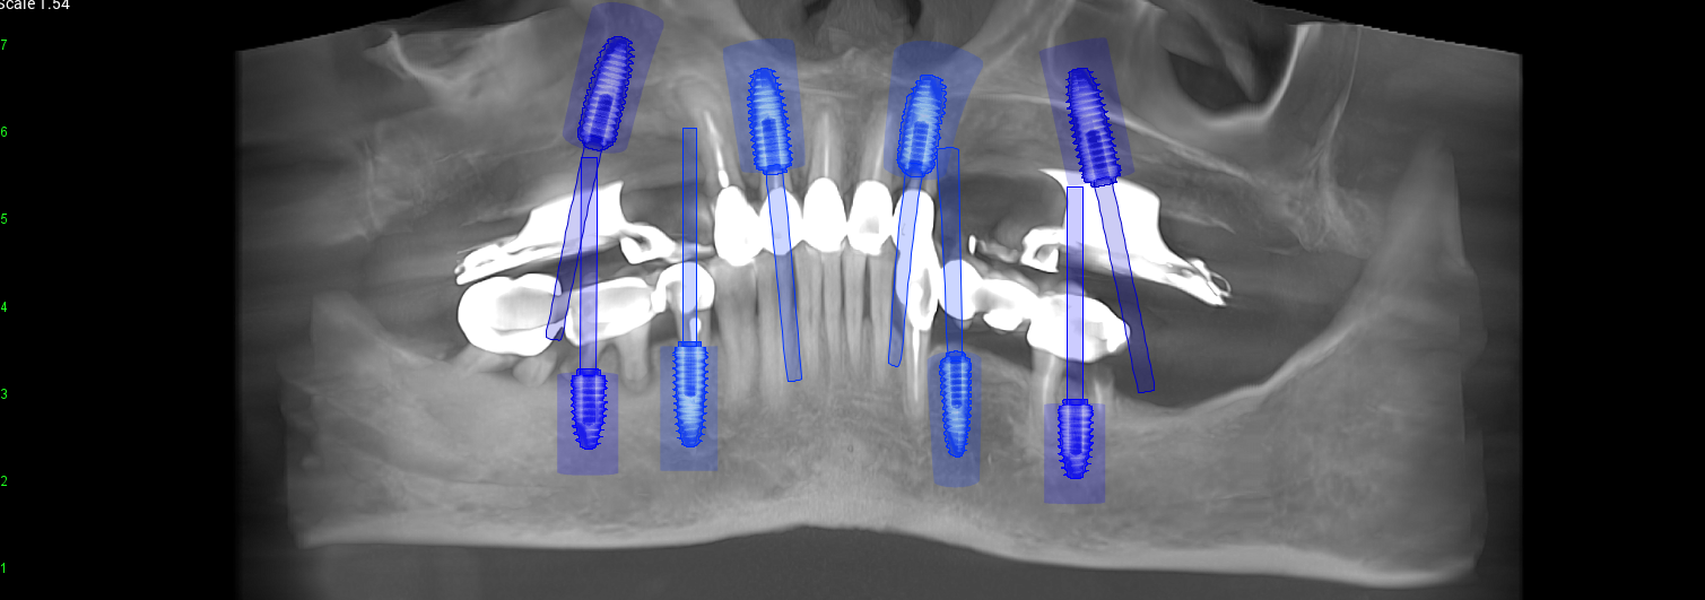

Tomografii (CBCT)

- Investigație imagistică completă, ideal CBCT (computer tomografie);

- Planificare computerizată a intervenției și, dacă este necesar, realizarea ghidului chirurgical;